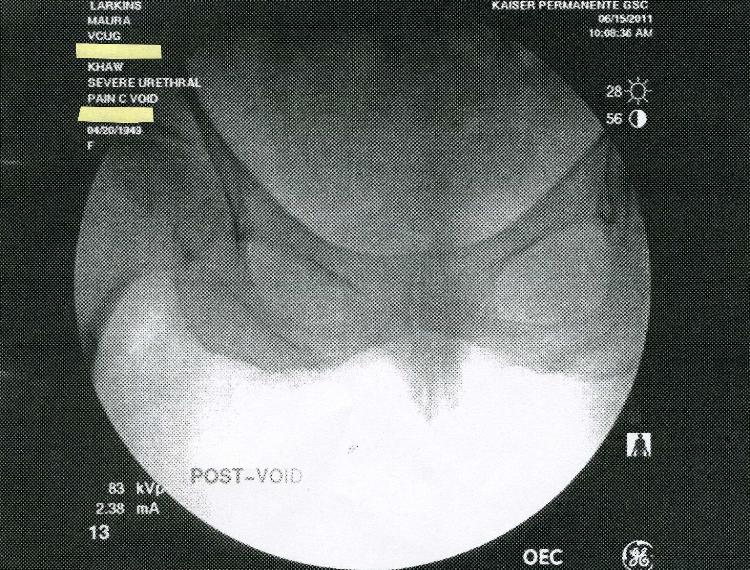

In July 2011 Kaiser Permanente in San Diego claimed that a large series of

X-rays done at the brand new Garfiled Specialty Center was not preserved on

film or saved electronically.  Kaiser claimed that only five images were

saved-on thermal paper! Below are the five images.  Incredibly, two of the

saved images are previews, or "scout" x-rays.  Why would these be printed

out?  They were not medically useful.  Answer: The truth is that all the images

were saved digitally, and Kaiser concealed them to cover-up an incorrect

diagnosis.